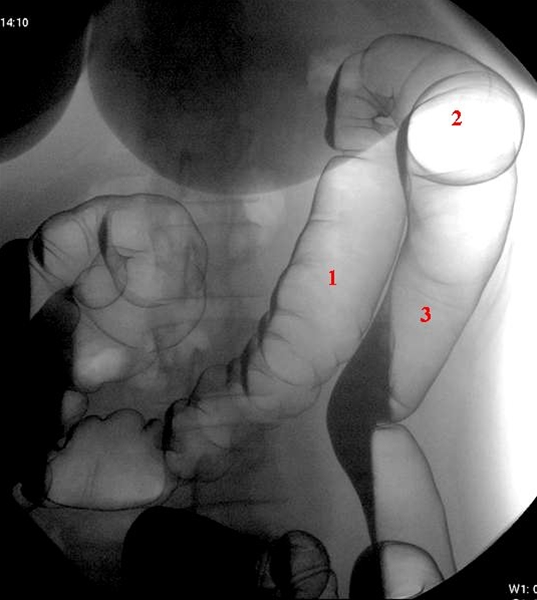

Venstre colonflexur i en optagelse med patienten i højre sideleje

1. Colon transversum

2. Venstre flexur

3. Colon descendens